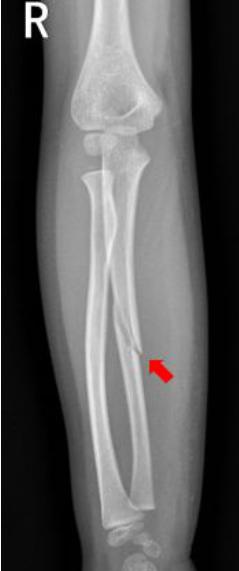

前臂

患儿摔倒,右前臂着地,拍片如下:

右侧尺骨中段可见斜形骨折线,骨折端稍分离移位,右侧尺骨中段骨折。